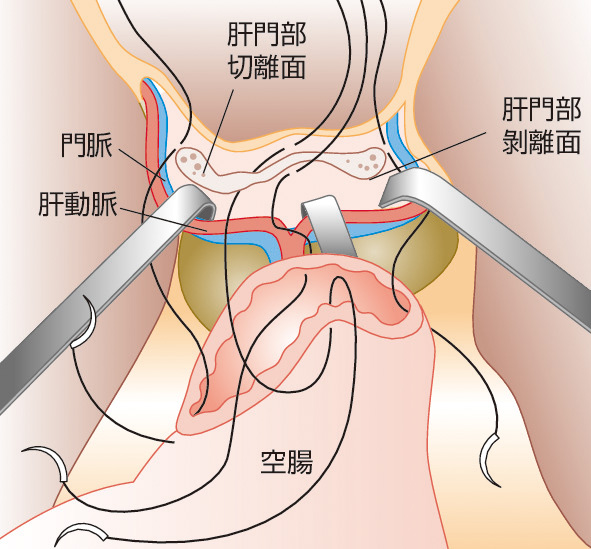

肝臓病学 朝倉書店 小児栄養消化器肝臓病学 | 日本小児栄養消化器肝臓学会 |本の詳細情報

小児栄養消化器肝臓病学 | 日本小児栄養消化器肝臓学会 |本。肝臓病学 朝倉書店 医学一般。朝倉内科学 第12版。朝倉書店『内科学』(第12版)デジタル付録。「肝臓病学」井廻 道夫 / 熊田 博光 / 坪内 博仁定価: ¥ 20000+税購入後、使うことなく埃や光が当たらない所で保管していました#井廻道夫 #井廻_道夫 #熊田博光 #熊田_博光 #坪内博仁 #坪内_博仁 #本 #自然/医療・薬学・健康